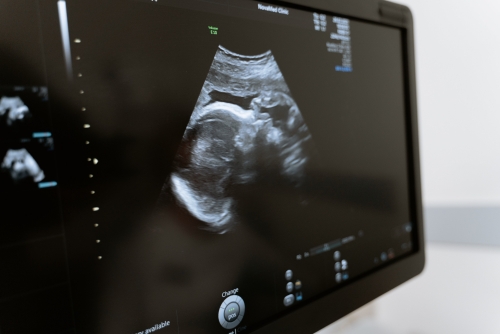

頸靜脈怒張可以做超聲檢查,超聲檢查是臨床常用的檢查手段,可以幫助發(fā)現(xiàn)頸靜脈內(nèi)血栓的常見診斷。而頸靜脈怒張常見于右心衰竭、上腔靜脈綜合征、肝硬化、腫瘤壓迫等疾病,因此可以通過超聲檢查明確診斷。

超聲檢測2